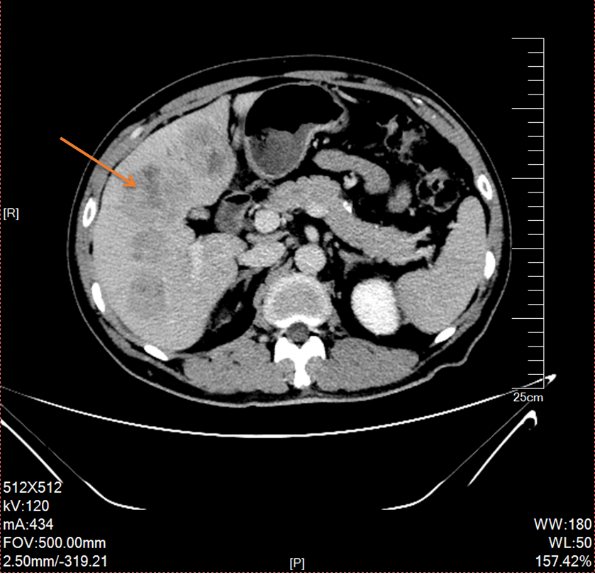

2019-03-14行上腹部增强CT,显示肝内散在的多发圆形稍低密度灶,大小不等,边界欠清晰,较大者直径约5.2cm,其内密度不均,增强扫描病灶周边有强化,内部有更低密度区液化坏死区,考虑转移瘤;胆囊多发结石;双肾多发结石,直径小于0.2cm;扫描范围内结肠肝区管壁增厚,管腔狭窄,增强扫描可见明显强化。

△2019-03-14上腹部(包括肝、胆、脾、胰范围内)平扫+增强